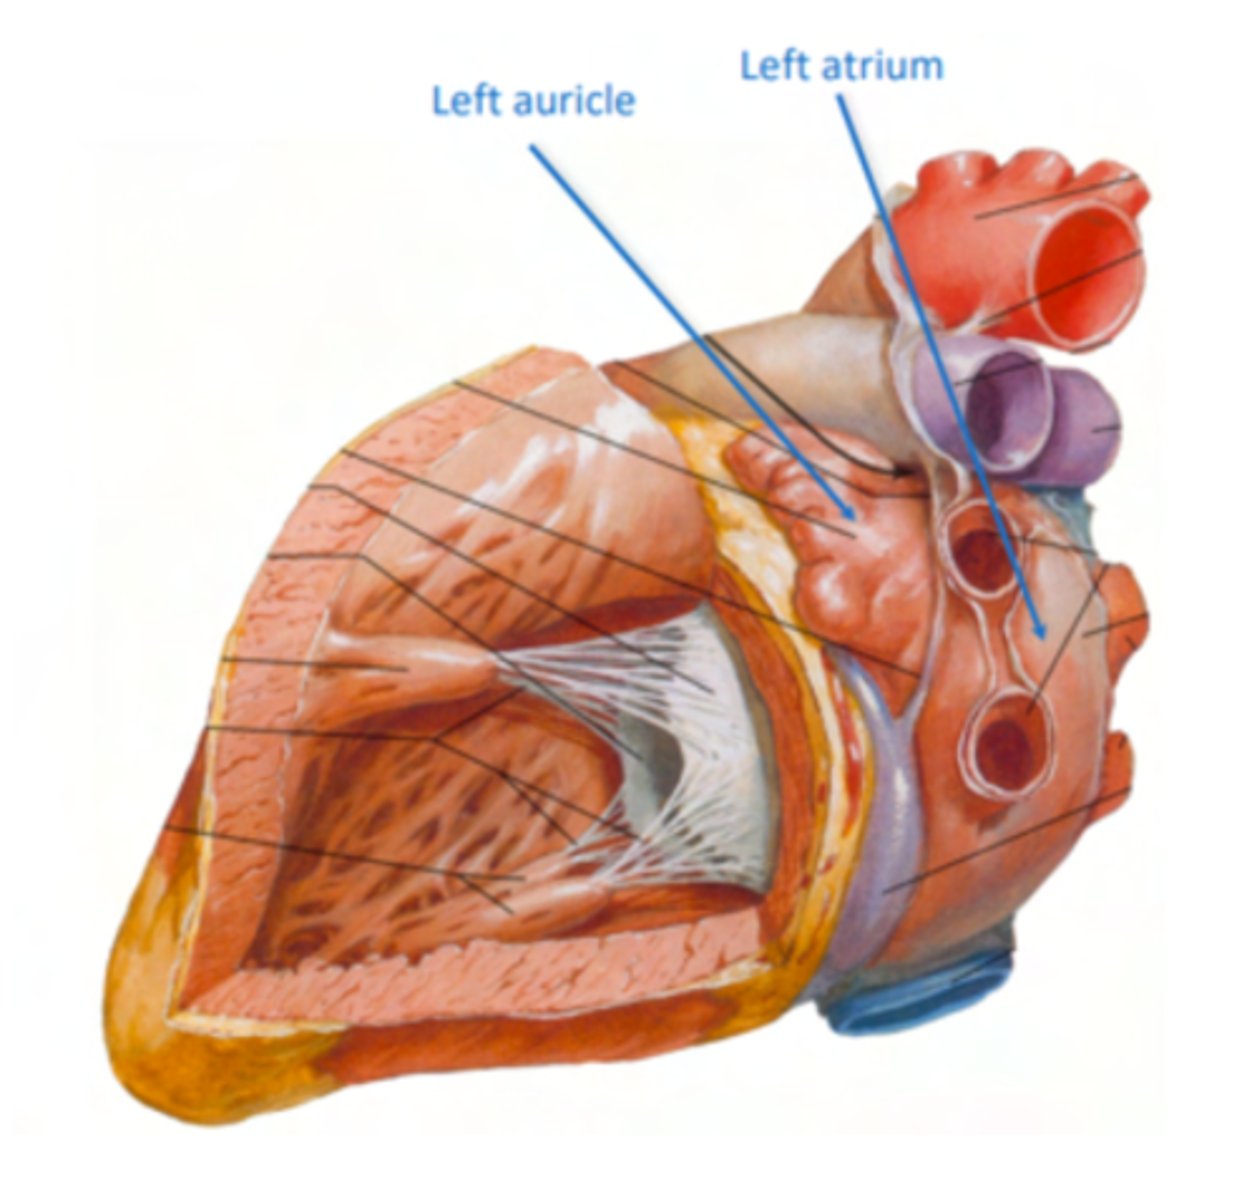

What are the atrial appendages?

Rough trabeculated region of the atria (Extensions of the atria)

External portions of the atria, (Real cavities of the right and left atrium being posterior to these auricles)

ALSO CALLED AURICLES

What are the two portions of the left atrium?

Smooth portion, originated from the incorporation of the

pulmonary veins. The proper atrium itself

Rough portion, the auricle or appendage,

SAME AS RIGHT ATRIUM